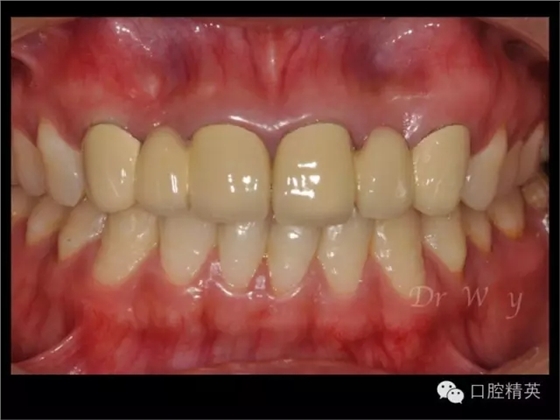

圖片11修復(fù)體完成像

圖片12修復(fù)前后對比口內(nèi)像